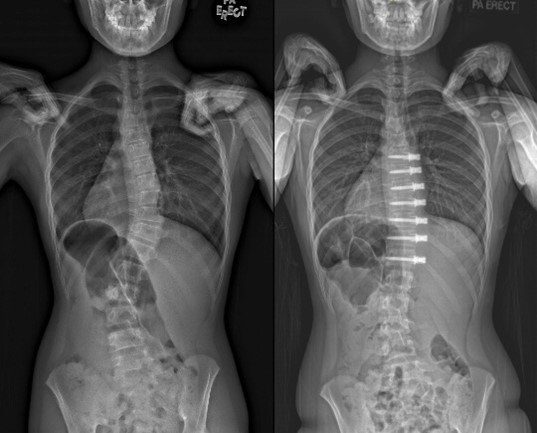

The Centre is also a recognised regional base for hands-on surgical training in thoracoscopic spinal surgery, spinal deformity surgery, cervical spine surgery, vertebroplasty as well as artificial disc replacement. The first of these instructional courses was conducted in 1990. In coordination with the National Scoliosis Screening Programme, the Spine Centre provides thoracoscopic, non-fusion (spinal tether) and conventional options for the surgical management of scoliosis. It was the first in the nation to perform artificial disc replacements of the spine in 2002. It has also sought to stay at the forefront of new and emerging techniques including endoscopic and minimally invasive spine surgery. In 2016, the Centre performed the first robot-assisted spine surgery in Singapore.

Amongst other achievements, the Spine group introduced interval halo-gravity traction for the treatment of very severe scoliosis curves, the use of O-arm navigated surgery employing paediatric radiation doses, the use of 3D printing in planning for complex spine curvature correction, the use of microdose EOS X-rays for scoliosis assessment, the intra operative use of spinal cord ultrasound post decompression to assess the adequacy of neural decompression and the introduction of endoscopic spine surgery.